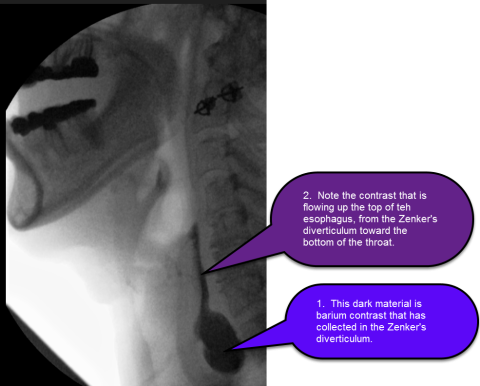

Zenker's diverticulum is diagnosed during upper endoscopy (EGD) or esophagram (aka barium swallow), or a modified barium swallow study (aka videofluoroscopic swallow study) (see figure). These tests complementary during investigation of swallowing problems.